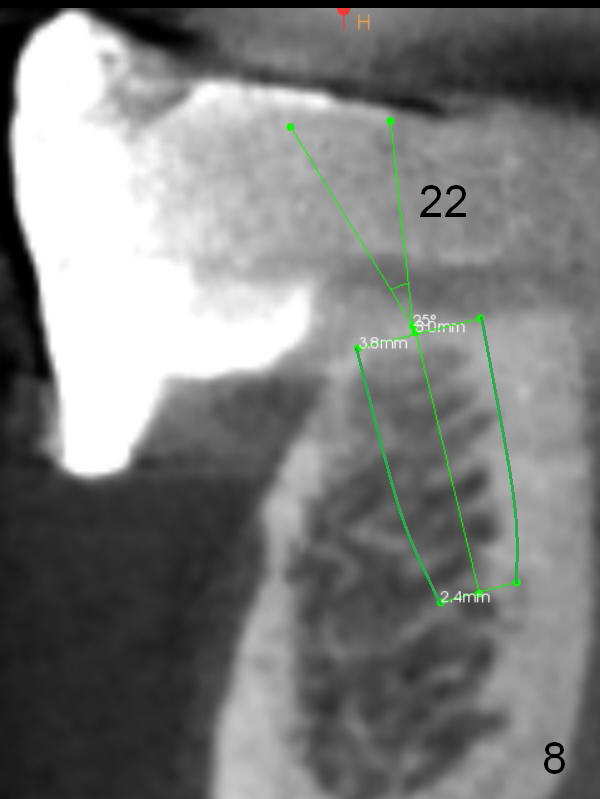

The patient wants to change unstable complete dentures to fixed ones.  Because the problem of pain is associated with the lower left (Fig.1 the left Inferior Alveolar Nerve is more superficial), the lower arch will be reconstructed first.  Totally 6 implants will be placed for bridges/crowns.  Due to time constraint, four implants are placed at the 1st stage (#21, 22, 27 and 28 (Fig.4,5,8,9)); the lower denture will be retained immediately by ball abutments and soft relined.  Two to three months later, two more implants will be placed (at #31 and 20, Fig.2,10).  Note severe atrophy of the crest at #18 and 19 (Fig.11 and 12).  If primary stability is achieved, a fixed immediate provisional will be fabricated.

In contrast to the upper arch, the bone density in the lower arch is high.  The challenge is bone height.  Short implants will be used (6 mm for #31 (Fig.2) and 8 mm for the majority of the others (at premolar and canine sites).  If needed, extra implants will be placed at incisor sites (Fig.6,7 (implant can be longer)) and at #29 (Fig.3) .  If a site is too small for a 3.8 mm 2-piece implant, a 1-piece one may be placed.